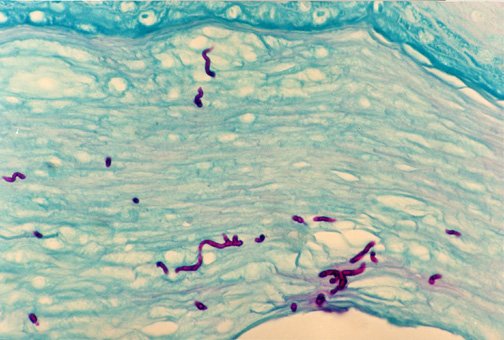

DERMATOHISTOPATHOLOGY:

PAS stain highlighting fungal elements in the stratum corneum. (PAS stain, 400x)